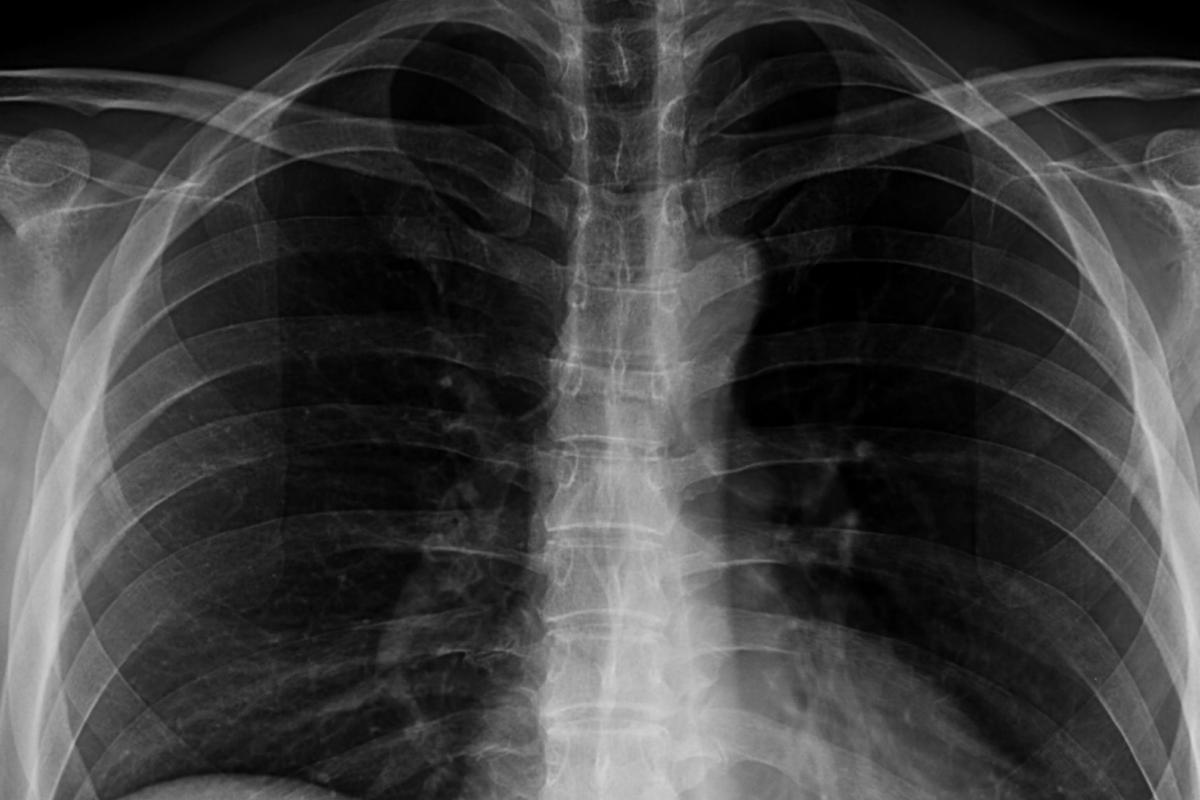

Su novio la llevó inmediatamente a urgencias, pero los médicos le dijeron que la cuchara era tan grande que era necesario programarle una gastroscopia. Por lo tanto, la mujer volvió a casa con la cuchara de 17 centímetros aún dentro de su cuerpo.

Finalmente, dos días después de tragarse accidentalmente la cuchara, los médicos la retiraron de su cuerpo. Para llevar a cabo la gastroscopia fue necesario suministrarle a Reymy anestesia local. "No me permitieron tragar mientras lo sacaban. Tuvieron que girarlo en mi estómago, lo que me provocó una pequeña hemorragia gástrica. No fue agradable, pero sentí un alivio absoluto cuando lo sacaron", ha detallado la mujer de 28 años.